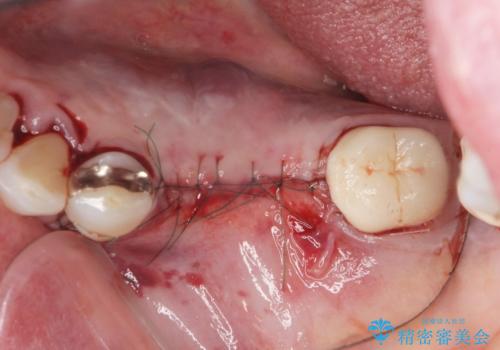

舌側にある大きな骨隆起を除去するとともに、除去した骨と人工骨を用いてインプラント周囲の骨を造成します。

自家骨と人工骨による骨造成は、長期的に見て安定し吸収が少ないとされる骨の造成法です。

インプラント周囲に、必要十分な骨を作ることが長期渡りインプラントにトラブルを起こしにくい鍵となります。